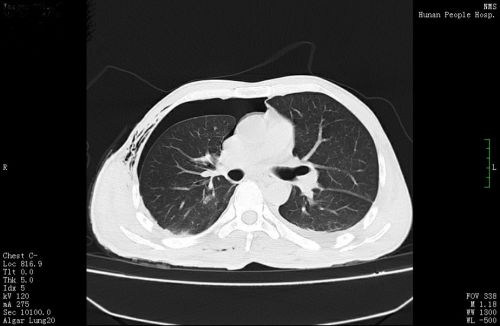

术前胸片提示,右侧胸腔内有一个巨大混杂密度包块(红圈内)。

胸部CT检查发现,其右侧胸、腹腔内有一个巨大包块压迫右肺,因此出现胸痛、胸闷等不适。进一步检查考虑,巨大包块来源于后纵膈,畸胎瘤的可能性大。心胸外科医师会诊后,将他收入心胸外科病房准备手术治疗。